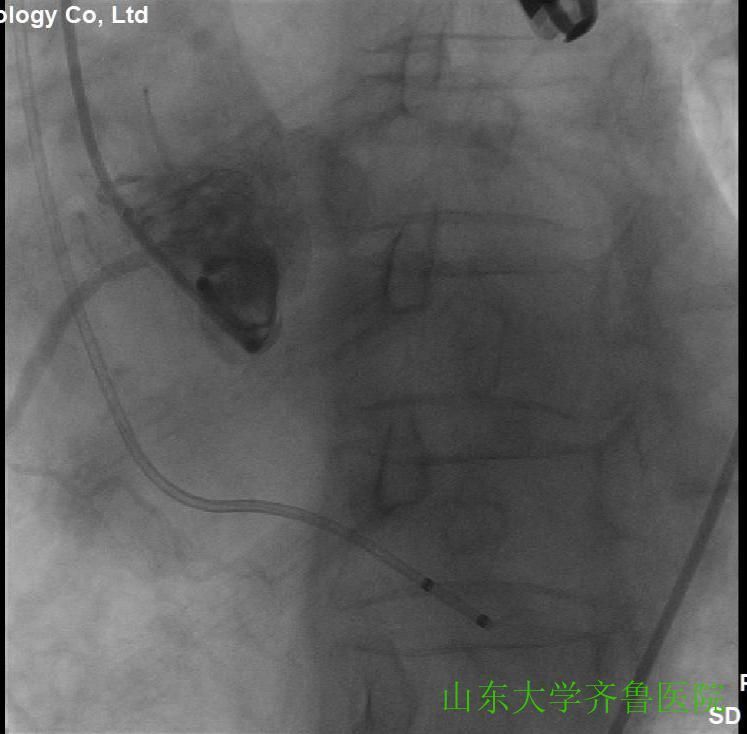

在手术室护士长翟永华及其护理团队、麻醉科吴剑波主任医师和杨绍忠主治医师的大力支持下,由心血管外科谷兴华主任医师、急诊心内科李传保主任医师、心内科安贵鹏副主任医师、心血管外科孙厚荣副主任医师及刘凯副主任医师、心脏超声室刘艳副主任医师和曹媛主治医师、放射科邵汉宏技师等在医院复合(Hybrid)手术室行一站式经导管主动脉瓣置换术(TAVR)+经皮二尖瓣球囊扩张成形术(PBMV)。手术先常规经颈静脉于右心室放置临时起搏导线并放置经食道TEE探头,行主动脉根部造影,明确主动脉瓣环平面、主动脉瓣钙化及返流情况(图1),导丝跨瓣入左心室并更换猪尾导管,测主动脉瓣跨瓣压差为76mmHg。选用24mm的擎源二尖瓣扩张球囊扩张2次,二尖瓣口面积由0.78?扩大至1.43?,并且二尖瓣无返流(图2)。选用20mmNuMed球囊,临时起搏心率180次/分,扩张狭窄的主动脉瓣(图3),应用26mmVenusA主动脉瓣介入瓣膜,准确定位、释放,造影、多体位透视及术中TTE显示介入主动脉瓣膜形态满意、无瓣周分流(图4-6)。术后即刻主动脉瓣最大跨瓣压差将至2mmHg。手术顺利,手术用时1小时40分钟,术后患者安返心脏外科监护病房。

图1主动脉根部造影,可见主动脉瓣环平面、钙化灶、主动脉瓣中度返流

图2应用24mm的球囊行二尖瓣球囊扩张

图3主动脉瓣球囊20mm扩张,显示左右冠状动脉,无主动脉瓣返流